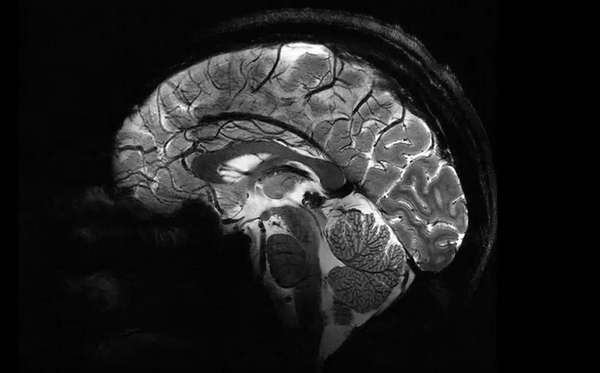

قدرتمندترین دستگاه MRI جهان ساخته شد

ICTPRESS - قدرتمندترین دستگاه ام‌آرآی جهان تصاویری از مغز انسان را در دسترس قرار داده که جزئیات و وضوح آن بی‌نظیر است.